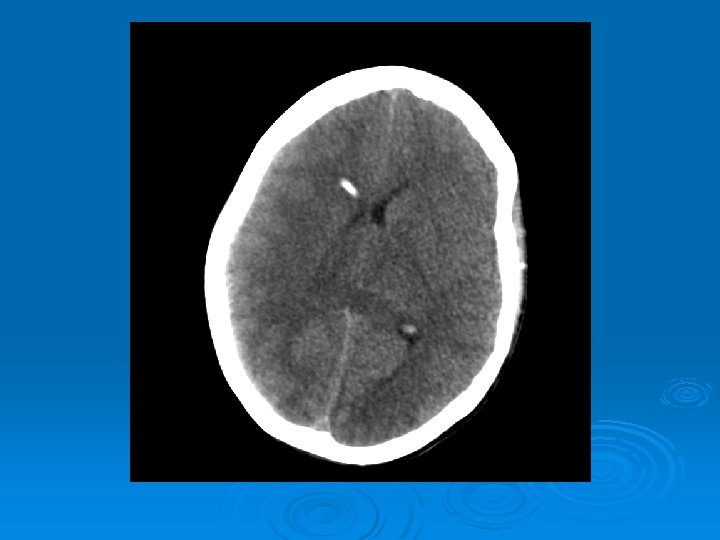

Course: Ø 3 PM, RN noticed anisocoria and L pupil non-reactive. Ø Neurology STAT dose mannitol and w/ dilantin. Ø Pt went for stat head Ct:

CT head 2/11/07 Ø A right frontal ventriculostomy catheter Ø Diffuse sulcal effacement with thickening of the cortex. Ø Loss of gray-white differentiation and hypodensity in the left parietooccipital region. Ø There is diffuse hypodensity of the cerebellum and brainstem. Ø Ø Ø The basilar cisterns are nearly completely effaced. Ø Impression: Ø Worsened diffuse cerebral edema The lateral ventricles are smaller

Course: Ø Neurosurgery saw pt: on exam she had lost cough, gag reflexes, corneal reflexes, she had flexed RUE, semipurposeful with bilateral extended LE. Ø Concern for herniation: placed Ø ICP 35 -40 10 th-11 th EVD